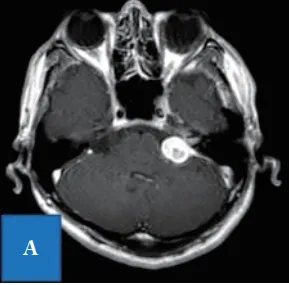

病史回顾:51岁男性,被诊断为听神经瘤约1年。未观察到面神经麻痹,但是左侧听力严重损失,仅为105dB。MRI结果显示肿瘤已进展至内耳道,直径为24mm。

(图1)根据影像学检查结果诊断为听神经瘤,术前头部计算机断层扫描血管造影(CTA)观察到在内耳道壁后方形成的颈静脉球(带骨图像)。

图1A:入院时T1-加权项磁共振成像显示,延伸到内听道的桥脑角均匀增强。